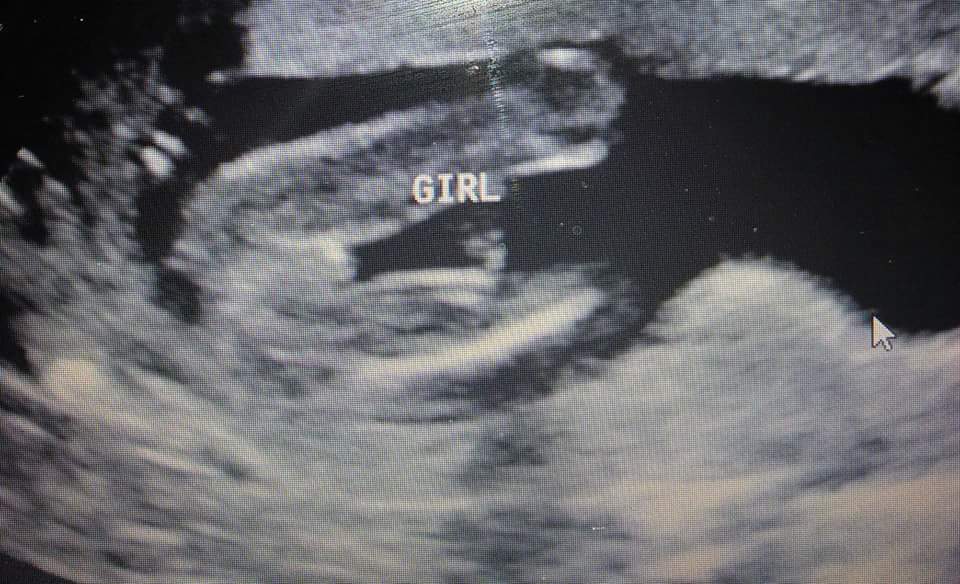

Had another scan today tech said 100%,girl! After 7,boys a dream come true!!!

Attachment 28584